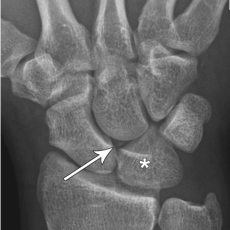

Luxation rétro-lunarienne du carpe

- Fracture associée du triquetrum

Altération arcs I et II de Gilula

- Fracture parcellaire du lunatum

- Bascule palmaire du lunatum avec trop bonne visibilité de sa corne dorsale (petite, pointue et postérieure)